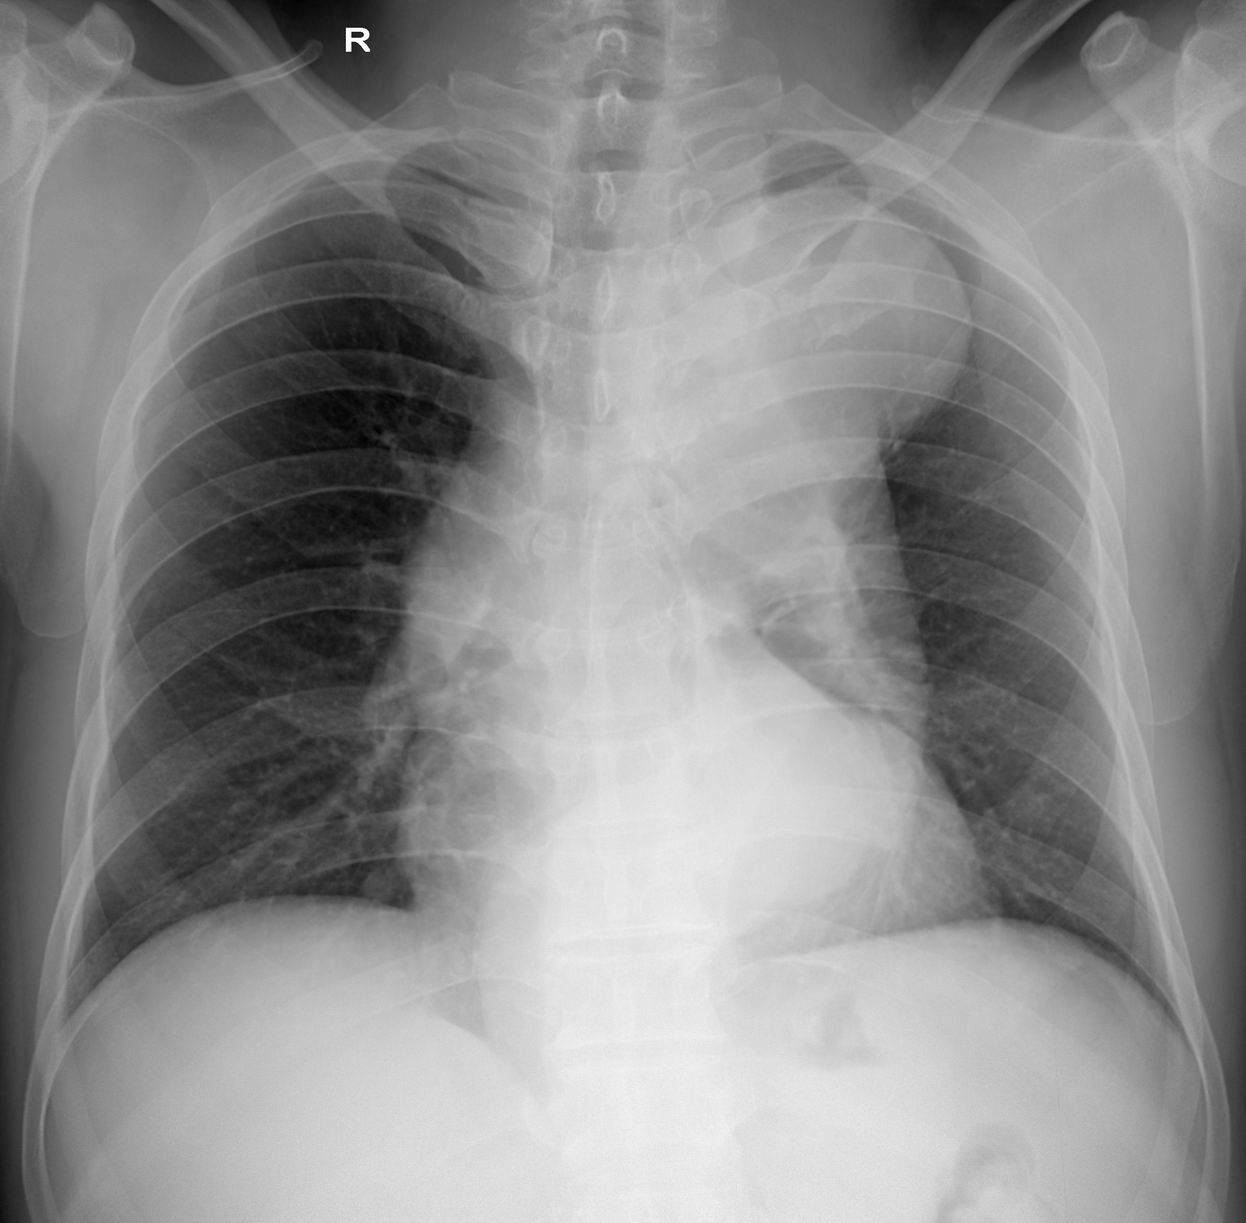

标题: x3216:间断咯血二天(结果在22楼)

间断咯血二天,bp:120/90mmmhg,心率100/分,律齐

标题: 经造影及mri 检查确诊为主动脉夹层

经造影及mri 检查确诊为主动脉夹层